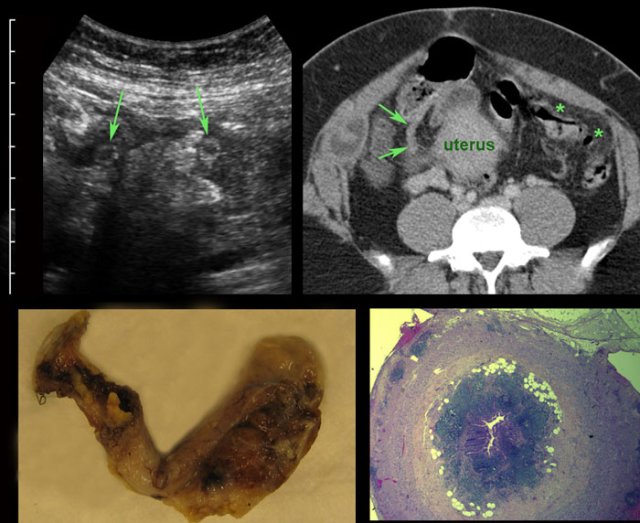

Torsion of enlarged adnex

case 1

Young female with acute onset of RLQ pain.

US

reveals a large mass filled with hypoechoic sebum, harbouring a hyperechoic hairball

(arrow) surrounded by multiple tiny linear

hair reflections.

CT confirms

a dermoid cyst containing a hairball

(arrow) and surrounded by fat stranding, caused by venous congestion.

At surgery

torsion of a dermoid cyst was confirmed.